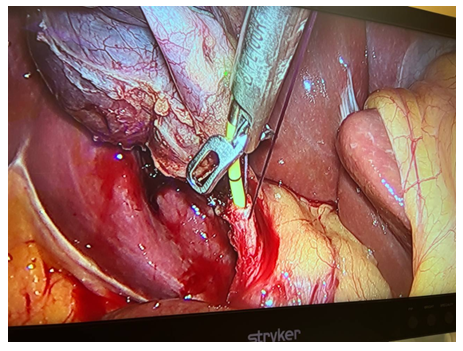

As can be seen from the table above, laparoscopic cholecystectomy was performed in 34 (56.6%) cases in patients with ACP; Laparoscopic cholecystectomy with assisted EPST using the Rendezvouz technique (LERV) – in 11 (20%) cases, and EPST and Laparoscopic cholecystectomy – in 7 (12.7%) cases with ACP combined with choledocholithiasis. In 10 (16%) cases of ACP in patients with concomitant somatic diseases and in elderly and senile patients, puncture interventions with drainage of the gallbladder under visual ultrasound control were performed at the first stage, followed by laparoscopic cholecystectomy at the second stage after improvement of the general condition of patients and indicators of endotoxemia, as well as adequate preoperative preparation, Of these, 4 have EPST supplemented at the 2nd stage.When performing LERV in patients of the first group (11 patients), the gallbladder was removed laparoscopically and the common bile duct was sanitized by endoscopic access through the Large duodenal papilla (LDP). At the first stage, after the cystic artery was isolated, it was clipped with a 5 mm titanium clip and crossed using an U-shaped hook using monopolar cutting. Next, the cystic duct was isolated at its maximum extent. After applying a 5 mm titanium clip to the cystic duct in its distal part, closer to the neck of the gallbladder, an incision of the cystic duct was performed below the applied clip to perform intraoperative direct cholangiography (Fig. 1, 2).  | Figure 1. Intraoperative cholangiography using forceps |